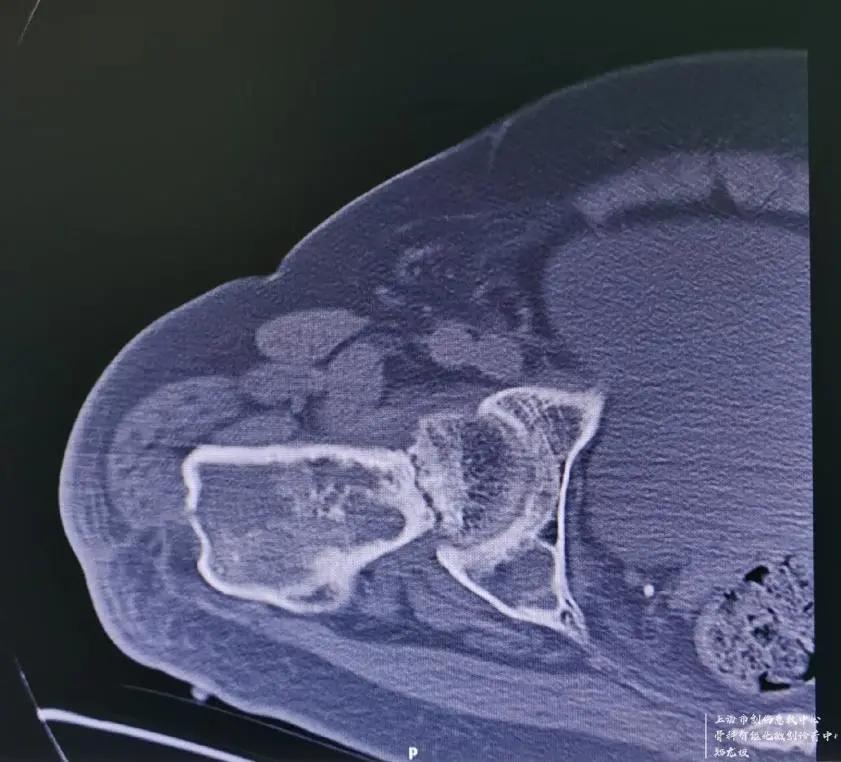

吴先生4岁时就得了右腿股骨的骨纤维结构不良的疾病,这种疾病又叫骨纤维异常增殖症,是先天性非遗传性疾病,主要病理改变是正常骨组织和骨髓被大量增生的纤维组织所替代,在纤维组织内有结构不良的骨小梁。临床上常导致疼痛、畸形、功能障碍及病理骨折,在我国占骨肿瘤样病损的首位。吴先生于1966年不小心摔倒后,导致右大腿骨纤维结构不良的部位病理性骨折,行牵引治疗后骨折愈合,后逐渐出现右大腿畸形短缩。

于1985年在某知名医院行右股骨干截骨矫形术,术后出现骨不连,截骨处假关节形成,内固定断裂,大腿畸形短缩进一步加重,左右腿粗细不一,长短相差近15公分,严重地影响了吴先生的正常生活、工作质量。吴先生曾经多次到知名大医院就诊,医生给出的建议是没有更好的治疗办法,也就宣判了吴先生右腿的终生残疾。此次摔倒雪上加霜的是,正好又摔断了畸形一侧大腿的股骨颈,新伤旧患叠加,让吴先生相当绝望!而让吴先生从绝望中起死回生的,是找到了十院骨科创伤中心主任郑龙坡教授------一个擅长啃骨科疑难杂症硬骨头的全国知名中青年专家。

经检查发现,如果是正常发育的大腿骨骼,可以根据骨折类型和患者的年龄不同,采取内固定或人工关节置换的方式进行手术。但由于吴先生右股骨近端骨纤维结构不良伴发严重畸形,且有断裂的内固定钢板存在,无法选择常规的治疗方式进行手术。

针对如此棘手的病例,且上海市血源非常紧张的情况下,郑龙坡教授团队经过充分的术前规划并与家属仔细沟通,决定分期对患者进行手术,一期对肱骨头骨折、肩关节脱位进行手术,二期采取肿瘤型假体置换的方式解决股骨颈骨折、股骨近端骨纤维结构不良伴严重畸形、股骨中段骨不连、内固定断裂等问题。

二期手术面临的最大的问题在于,股骨近端从股骨头至股骨中段骨不连这一段要整个拿掉,创面相对比较大,同时针对患者最关心的患侧肢体短缩15cm的问题,最大程度延长到多长,能否和健康侧一样长且不会导致下肢血管和神经的损伤,是重点考虑的问题。

按照预定计划,患者一期进行了肩部的手术,手术及术后康复锻炼非常顺利。二期股骨手术,先把原来断裂的内固定物取出,再把畸形愈合的股骨近端从骨不连的地方切除,同时切除周围大量增生的骨痂,安装定制的人工股骨近端假体,并重建周围软组织平衡,历经2个小时的奋战,手术顺利完成。